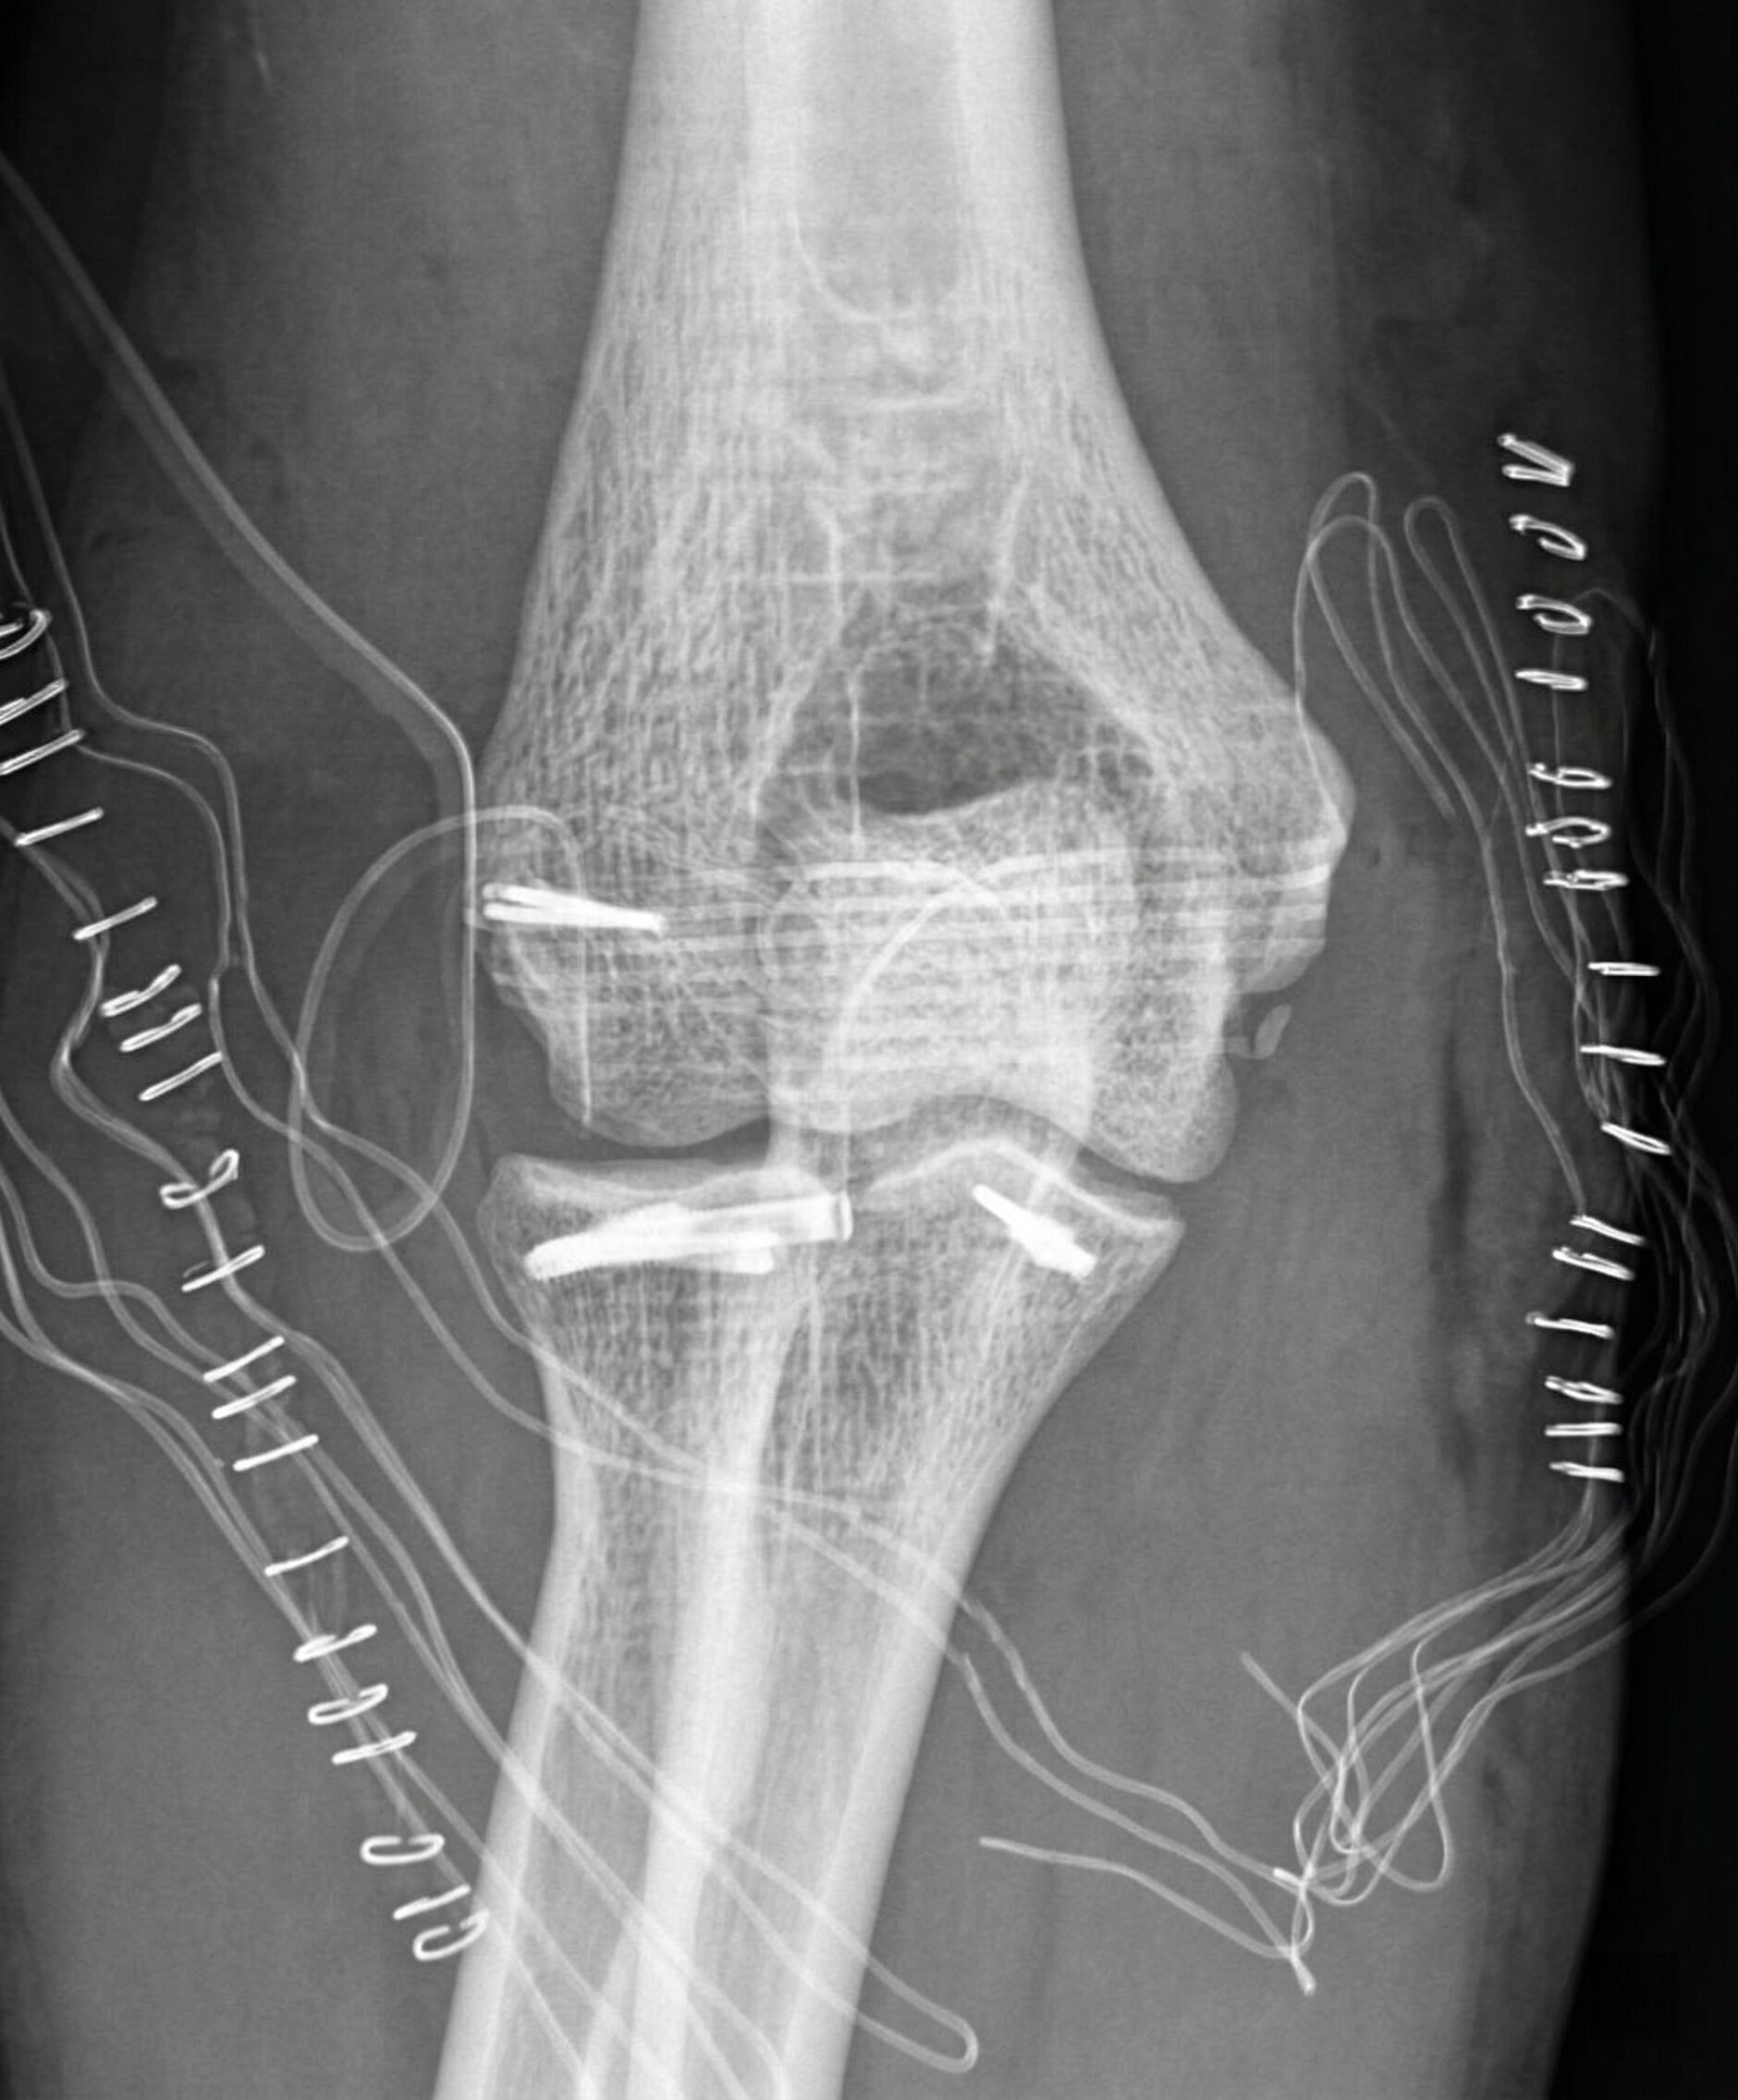

Comprende fratture e lussazioni causate da traumi. Il trattamento varia da immobilizzazione a chirurgia soprattutto per le fratture che coinvolgono i segmenti ossei inclusi nelle articolazioni, oppure per le fratture scomposte.